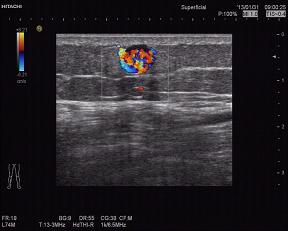

超声所见:右小腿肿物处皮下脂肪浅层可探及一0.7*0.73㎝低-无回声结节,边界清,CDI:其内充满血流信号,可见动脉频谱,并可见其右侧有一支动脉进入,检查过程中血流信号逐渐消失,此时患者自觉局部疼痛,观察5分钟后血流信号逐步恢复丰富状态。

超声提示:右小腿脂肪浅层结节—血管球瘤可能。病理结果为(右小腿)平滑肌瘤。